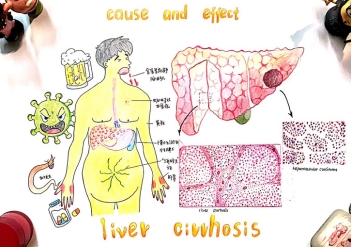

作品名:《肝硬化的前因后果》

作品简介:本作品以肝硬化为切入点,分别从大体观和镜下显微观描绘了肝硬化,以及肝硬化发展成的肝细胞性肝癌。描绘了肝硬化的成因:病毒性肝炎,慢性酒精中毒,药物及化学毒物,血吸虫虫卵沉积等,以及肝硬化的临床病例联系:慢性淤血性脾大、腹水、侧支循环形成、胆色素代谢障碍、对激素的灭活作用减弱等。还描绘了晚期肝硬化引起的并发症肝细胞性肝癌。用夸张的手法表现出肝硬化的危害性。希望可以通过本作品让人们认识到肝硬化的危害。